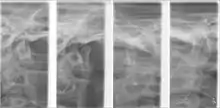

Plain radiography

This method of imaging allows the visualisation of the joint's mineralised areas, therefore excluding the cartilage and soft tissues.[53] A disadvantage of plain radiography is that images are prone to superimposition from surrounding anatomical structures, thereby complicating radiographic interpretation.[53] It was concluded that there is no evidence to support the use of plain radiography in the diagnosis of joint erosions and osteophytes.[54] It is reasonable to conclude that plain film can only be used to diagnose extensive lesions.[54]

Panoramic tomography

The distortion brought about by panoramic imaging decreases its overall reliability. Data concluded from a systematic review showed that only extensive erosions and large osteophytes can be detected by panoramic imaging.[54]